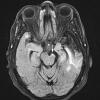

VASCULAR

Infarct, Tract Degeneration, illustrative case (2)